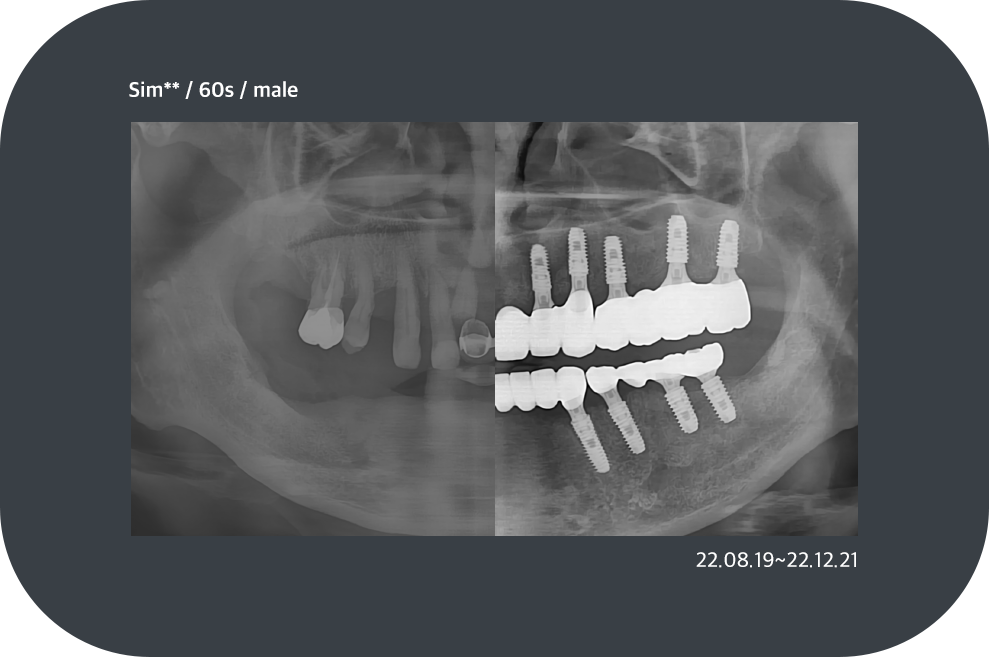

전체 임플란트

충치, 잇몸질환, 사고 등의 이유로

치아가 전부 상실된 경우

고정식으로 치아를 모두 재현하는 시술로 기능 회복 뿐만 아니라

전반적인 상황을 고려해야 하므로 경험이 많은 시술자에게 받아야 합니다.

치료사례

임플란트 치료사례

*모든 증례 사진은 의료법 제23조, 제56조에 의거하여, 당사자의 동의하에 게시하였습니다.

*치료 사진은 모두 본원에서 치료한 환자분의 사진입니다.

*치료 사진은 모두 동일인의 사진이며, 동일조건에서 촬영하였습니다.

*개인의 차이에 따라 시술 및 수술 후 부작용이 발생할 수 있으며, 의료진과 충분한 상담을 받으시기 바랍니다.